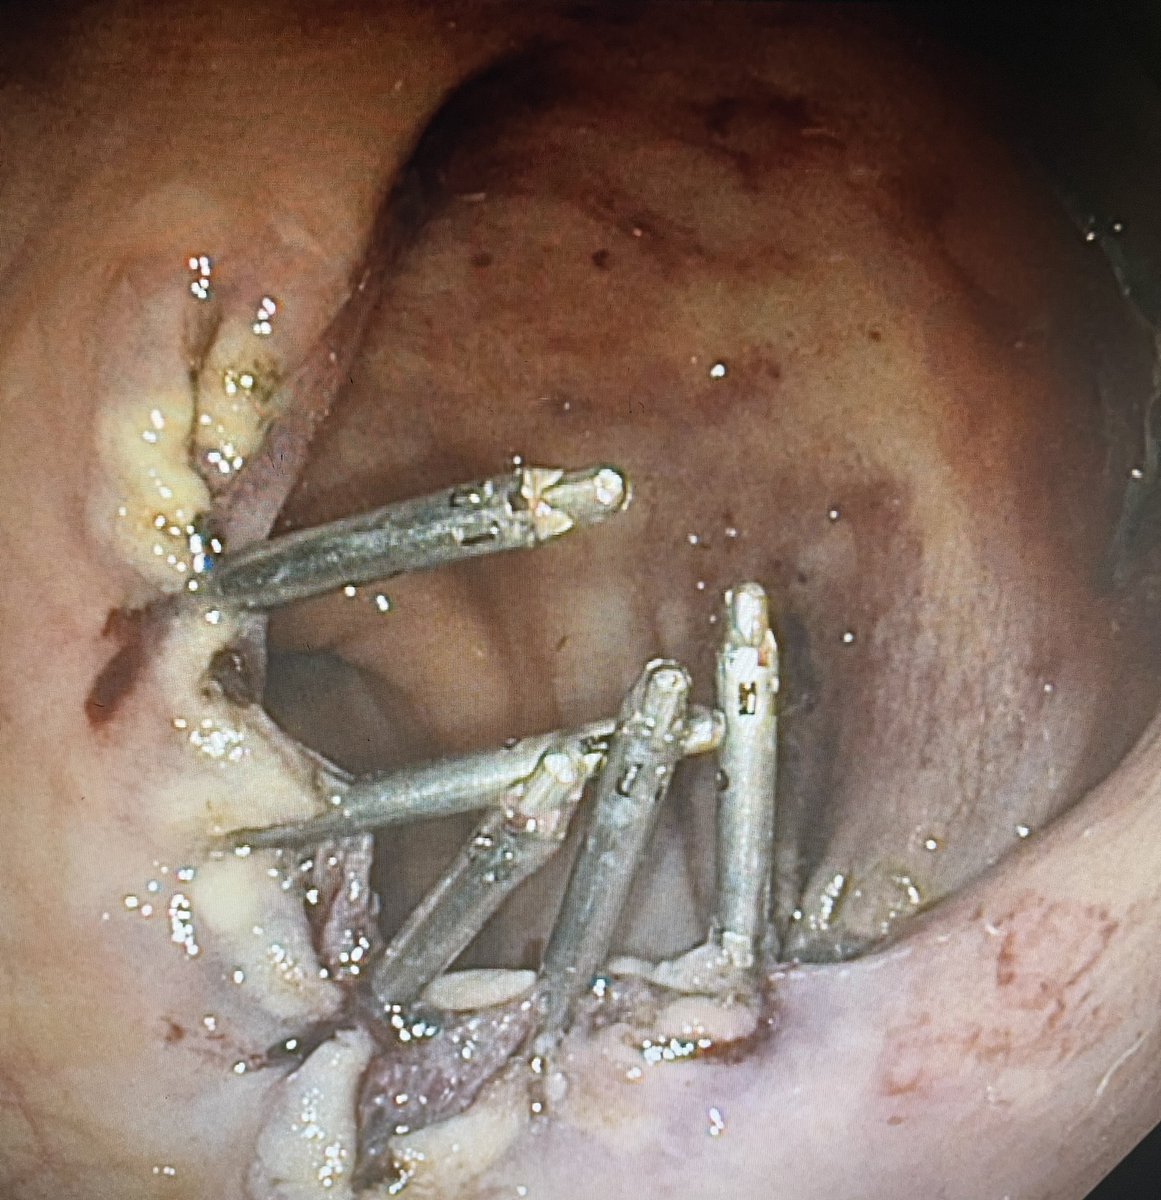

Distal duct diameter relative to size of stone a determinant of “difficult stones”. For stones above a stricture suggest use of @cookmedical fcSEMS to remodel before attempt at stone clearance. See how @gwebster_endo and @tmenabawey did it. Join us Thursday 1800 GMT for GL: LIVE

@GastroLearn @CookMedical @TMenabawey Stones above strictures a real challenge! We’ll be discussing optimal management (and all things stones!) 1800-1830 GMT Thurs April 14th ‘Between a Rock and a Hard Place’ Join free @GastroLearn #GITwitter @BritSocGastro @ESGE_news @helpatologist @drkeithsiau @EndoscopyNow